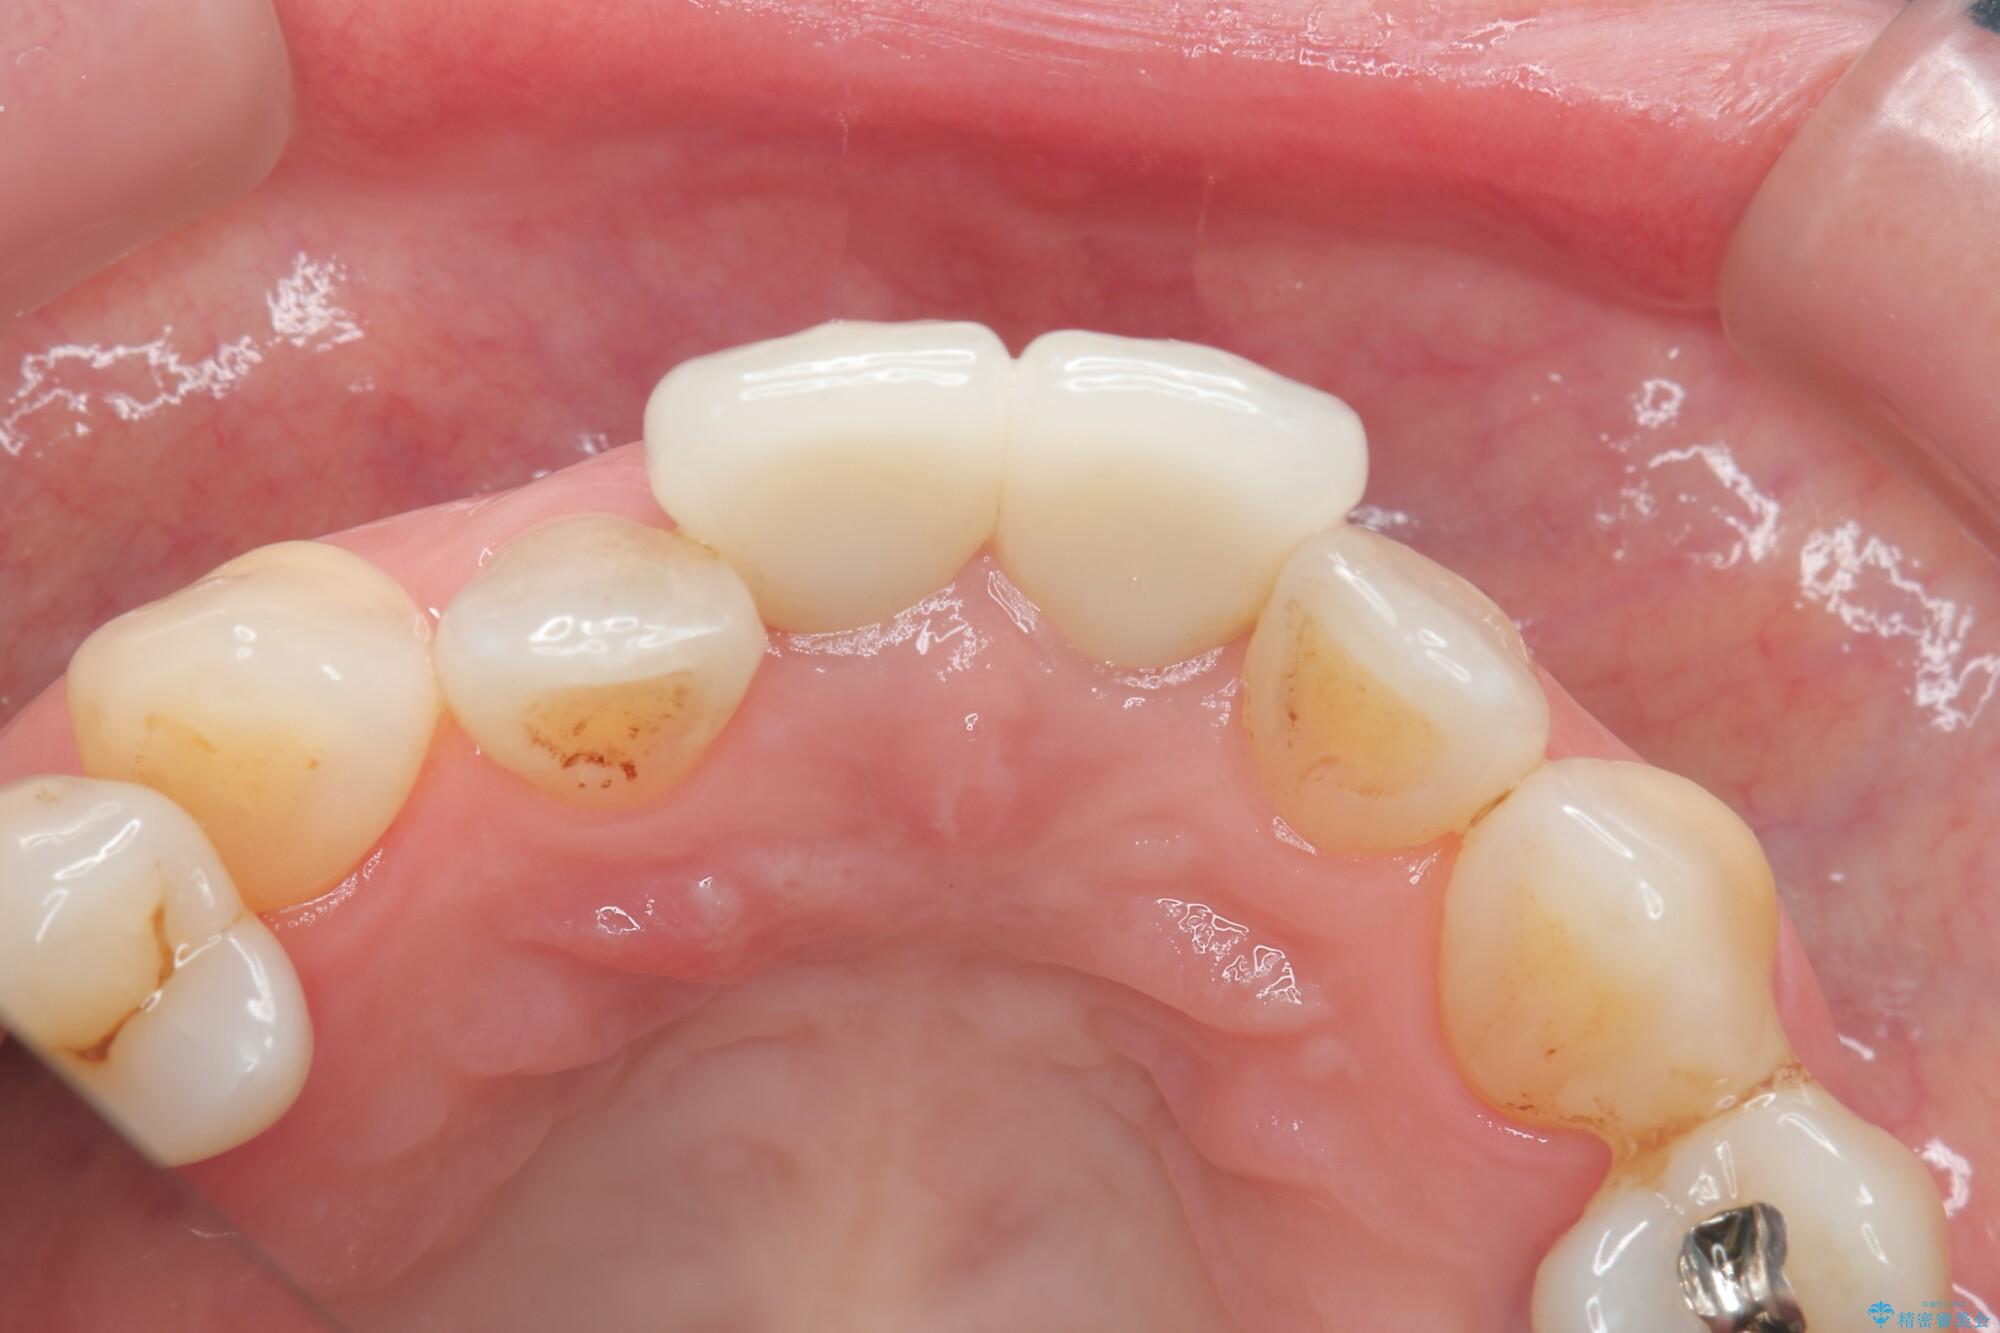

前歯の差し歯(クラウン)が黒ずんでいるとご相談にいらっしゃった患者様です。

根管治療は行わず、クラウンのやり替えのみ行います。

審美性に優れるジルコニアクラウンによる治療を計画します。